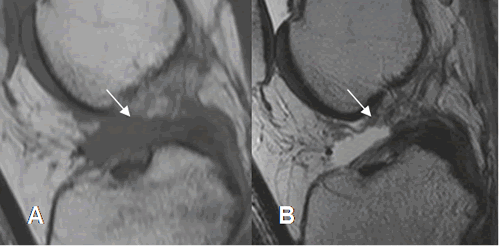

Fig 99. Ruptura crónica del LCA.

A: RM sagital en T2 y B: RM sagital en STIR. LCA engrosado (Flechas gruesas) persistiendo escasas fibras en la parte proximal, por ruptura crónica.